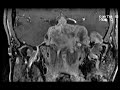

Myxoid Sarcoma of the Skull Base

These images show a massive, heterogeneously enhancing, T2 hyperintense mass with large intra and extraosseous components markedly expanding the nasal cavity and paranasal sinuses (left greater than right), sella and cavernous sinuses, left petroclival synchondrosis with large dumbell shaped extension into the left cerebellopontine angle and left mastoid. There is moderate mass effect on the left brachium pontis and temporal lobes and marked left proptosis. There is mild mass effect on the optic chiasm. There is no restricted diffusion. Pathology showed a myxoid sarcoma. These lesions are characterized by T2 hyperintensity and enhancement which is seen here. They are usually seen in young to middle age adults as seen here, but they are most commonly located in the lower extremities with the skull base location being very uncommon.